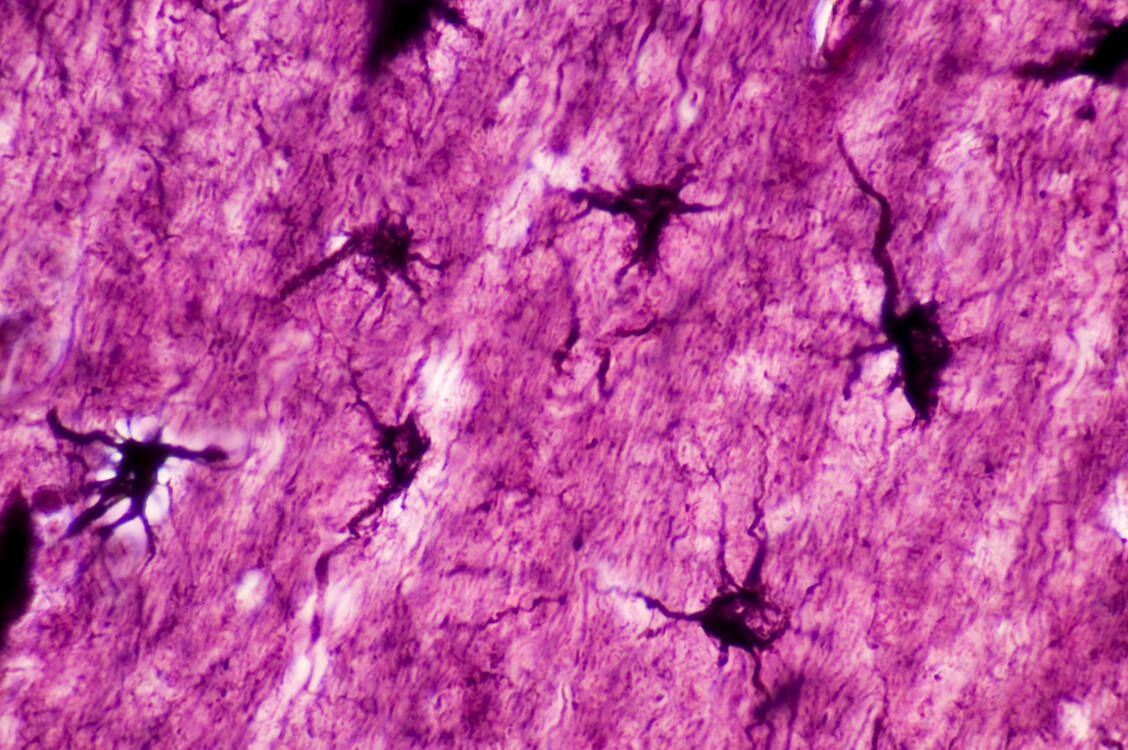

Für Patienten mit bestimmten Hirntumoren steht ab sofort eine neue Therapieoption zur Verfügung: Vorasidenib hemmt die beiden Isoformen der Isocitrat-Dehydrogenase IDH1 und 2 und darf bei Gliompatienten...weiterlesen »